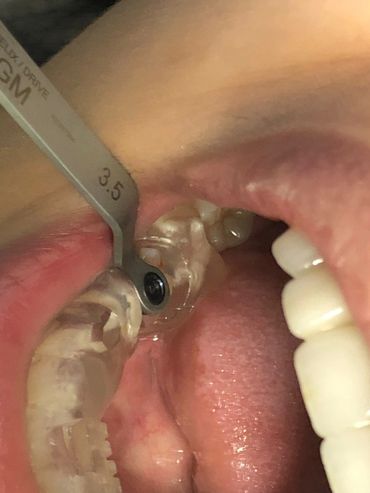

All implant drivers are provided with

indexer (Exact) markings to guide

implant installation, according to

prosthetic rehabilitation

The Neodent® EasyGuide Sleeve is selected according to mesiodistal space and implant diameter.

The Neodent GM Guided Surgery Kit is a compact, easy to use guided surgery system. Clinicians can provide CT scan, digital photos, and impressions to a laboratory for precise implant guide fabrication. Temporary teeth can be made and the lab will know the depth, angle, and timing of the connection of the implant. This allows you better esthetics and provides the patient teeth the same day with less chair time.